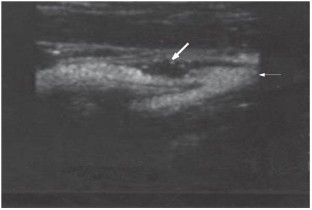

Shah F et al. (2007) Contrast-enhanced ultrasound imaging of atherosclerotic carotid plaque neovascularization: a new surrogate marker of atherosclerosis? Vasc Med 12: 291–297

Carlier S et al. (2005) Vasa vasorum imaging: a new window to the clinical detection of vulnerable atherosclerotic plaques. Curr Atheroscler Rep 7: 164–169

Vavuranakis M et al. (2007) Detection of perivascular blood flow in vivo by contrast-enhanced intracoronary ultrasonography and image analysis: an animal study. Clin Exp Pharmacol Physiol 34: 1319–1323